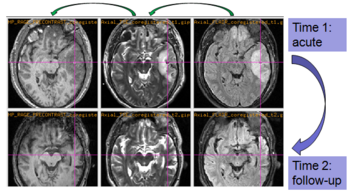

Experiments: Registration of longitudinal data

The NA-MIC DBP project on TBI analysis (UCLA partner) includes serial multi-modal MRI at acute phase and follow-up after six months. We test mutual-information-based linear registration of multi-modal MRI data within each time point and nonlinear registration (b-spline) of follow-up scans to obtain sets of images mapped into the same coordinate system. Preliminary results demonstrate the large deformations due to mass effect of a large lesion but also significant large regional changes of multi-modal MRI contrast from actute to follow-up.

Longitudinal co-registration of multi-modal MRI.